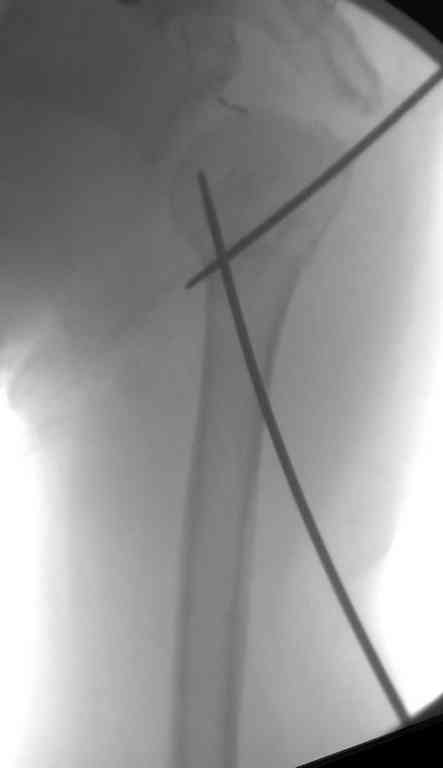

Сделали напряженными спицами по методике А.Ф.Лазарева со товарищи Репозиция сделана спицевым дистрактором, проксимальная спица была проведена в полскости деформации перпендикулярно оси наклонившейся головки. Получилось все довольно легко. Спицы малость покороче можно было сделать, ну да удалять потом легче будет.

Картинка в приложении.

Очень даже неплохо получилось. Молодцы! Лучше чем на 3D "репозиции".

Все заняло 1 час. Собственно введение фиксаторов - минут 20.

Оставили в косынке, сразу разрешены маятникообразные движения в плечевом суставе. Дальше по ходу расскажу.